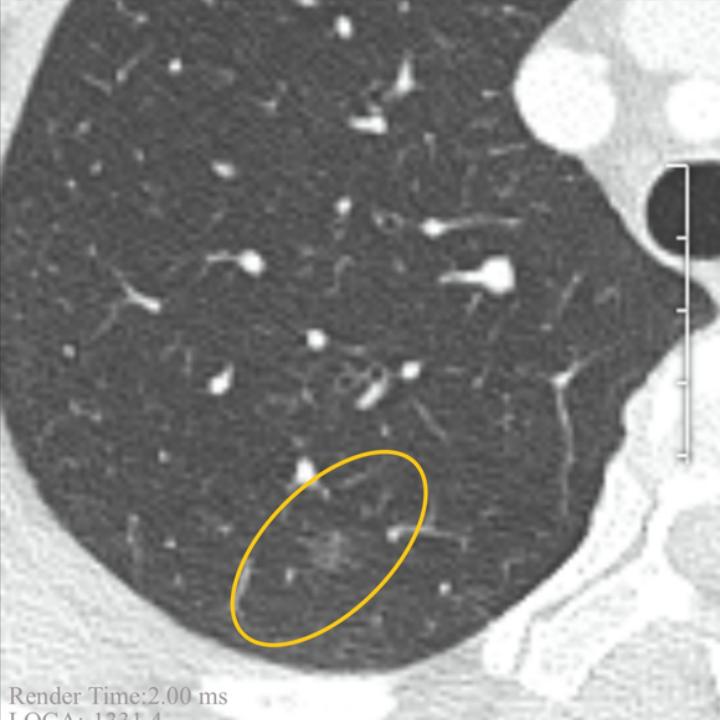

因为爱人刚经历大手术与放疗不敢轻易再进行手术,所以恳请戴主任白忙之中给到看片和答复。也请吧友帮我顶贴,谢谢大家了!,图1,2是2022年12月的pect ct拍的,图3图4是5月19日的片子。拜托了,给大家磕一个。

两侧胸廓对称,右肺上叶后段见不规则磨玻璃密度结节影,边界较清楚,直径约6mm,FDG摄取未见异常。右肺下叶后基底段实性小结节,直径约4mm,FDG摄取未见异常。右侧胸膜钙化灶;两侧胸腔无积液。右肺门、气管前腔静脉后见数枚小淋巴结,部分小钙化灶,大者短径约6mm,FDG摄取稍增高,SUVmax=2.1。

右肺上叶后段磨玻璃密度结节,FDG代谢未见异常,考虑不典型腺瘤样增生可能,建议CT随访复查。右肺下叶后基底段慢性炎性小结节。右侧胸膜钙化灶。右肺门及纵隔数枚慢性炎性小淋巴结,部分伴钙化灶。